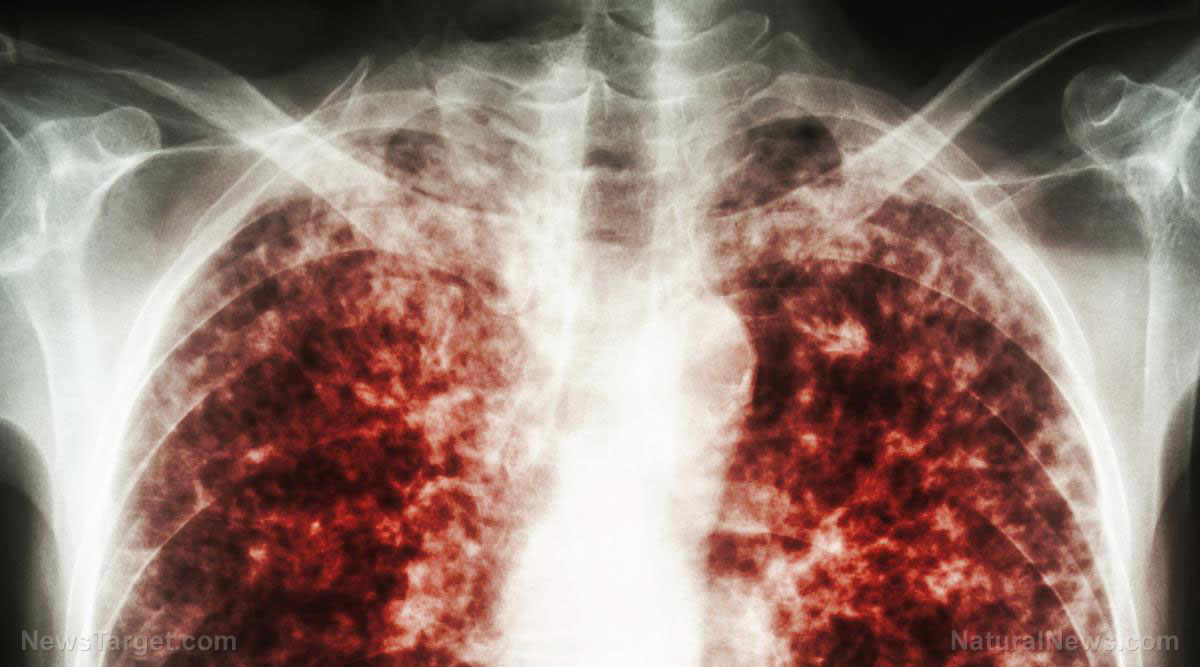

Cover-up of tuberculosis outbreak at Cape Cod migrant encampment EXPOSED by local media

A local radio talk show and a conservative newspaper in Massachusetts have exposed the coverup of a tuberculosis (TB) outbreak at a Cape Cod migrant encampment. On Dec. 2, 2023, CEO Heidi Nelson of the Duffy Health Center sent an emergency alert email to Democrat Reps. Kip Diggs and Christopher Flanagan, Democrat Sen. Julian Cyr and Republican […]

Cases of white lung syndrome reported in the U.S. and China

Reports in the Chinese media of children experiencing a mysterious respiratory illness have the world on edge wondering if the next pandemic could be about to emerge – and used as an excuse to infringe on our freedoms. The illness, which is being referred to as “white lung syndrome” in some circles, has already started […]

U.S., Sweden and Switzerland now experiencing a SURGE in pneumonia cases while China deals with “white lung syndrome”

Experts are worried after an alarming number of pneumonia cases have been detected in Sweden and Switzerland, especially as it follows a similar surge in cases in China. Denmark and the U.S. have also recently reported an increase in cases of a similar respiratory infection in children. Ohio also dealing with pneumonia cases A recent study revealed that […]

WHO monitors mysterious pneumonia cases among children in China, which experts say are “concerning” but likely not due to a new COVID variant

The World Health Organization (WHO) is looking into an alarming increase in respiratory illness among children in China. The cause of the reported pneumonia cases is unclear, but some health experts think that it is a common and temporary aftereffect of lifting pandemic lockdown restrictions. The unanswered questions surrounding the recent infections have raised concerns due to parallels with […]